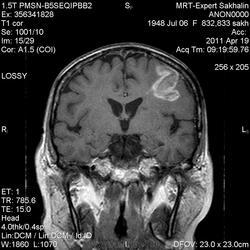

склоняюсь к кровизлиянию в левой теменной долей, начало перехода острой стадии в раннюю подострую( по периферии определяется повышение МРС по Т1 ВИ -метгемоглобин). Справа -старые кортикальные постишемческие глиозно-атрофические изменения. Контрастируется , вероятно за счет формирования участков ангионеогенза.

А мне кажентся больше за опухоль. Может быть сосудистая мальформация. Клинико-анамнестические данные есть?

Это демиелинизирующий процесс, острая стадия, причем с геморрагическим пропитыванием в центре пораженных участков. В принципе, соответствует тяжелому рассеяному склерозу, хотя может быть и геморрагическая форма ОДЭМ. Также могут быть мозговые проявления системного васкулита: надо знать анамнез.

На фоне ДЭП изменений МР-картина ОНМК по ишемическому типу в бассейне ЛСМА с участками геморрагического пропитывания. Аналогичный участок но в более поздней фазе в задних конвнкситальных отделах правой теменной доли.

О.С., я согласен, что контрастирование нехарактерно для ОНМК, ведь в подострую стадию инфаркта наблюдается, как правило, гиральный тип усиления. Плюс, на ОНМК непохоже то, что поражено почти только белое вещество, а кора интактна. И потом, при такой локализации инфаркта обязательно должна быть яркая клиника, и уж никак не только "головная боль".

Что касается снимочков мне кажется что зона патологического сигнала в левой гемисфере можно расценить как подострую стадию ОНМК с геморрагическим пропитыванием, справа как последствия ОНМК. При чем множественные очаги скорей всего как проявление ХМНК. И обязательно рекомендовать контрольное МРТ в динамике . Если это действительно ОНМК на фоне лечения отек уйдет и будет формированиться зона кистозно-глиозных изменений, а если отек будет нарастать значит надо думать о объемном процессе.

ОНМК по геморрагическому типу, почти классика.